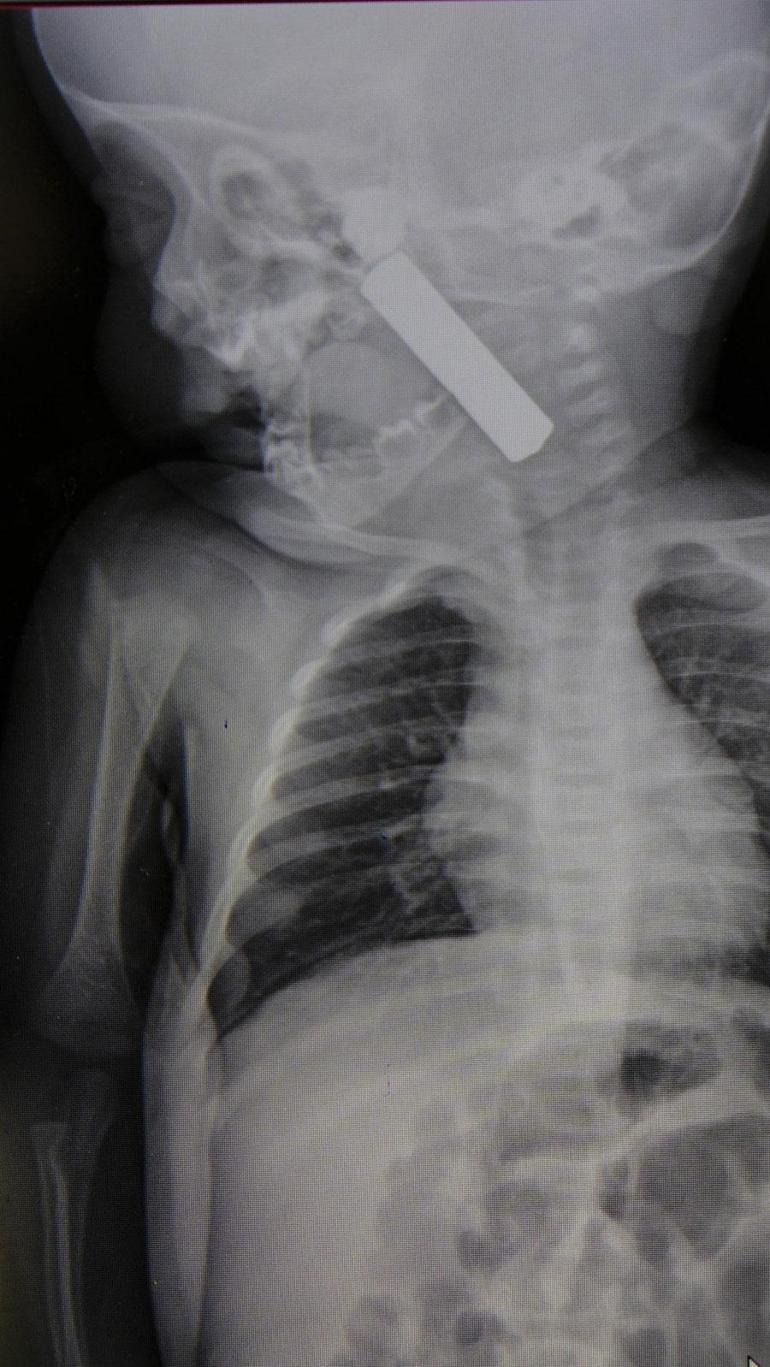

Edinilen bilgiye göre, kusma şikayeti ile ailesi tarafından Karaman Eğitim ve Araştırma Hastanesi acil servisine getirilen 6 aylık E.A. isimli kız bebeğin, yapılan muayene ve tetkiklerde boğazında kumanda pili kaçtığı tespit edildi.

Yaşanan olayla ilgili bilgi veren Doç. Dr. Mehmet Uysal, "Acil polikliniğimize kusma şikayeti ile 6 aylık bir kız bebek getirilmiş ve bize haber verildi. Biz de vakit kaybetmeden geldik, hastamızı gördük. Yapılan tetkikler sonucunda, ağız tabanına oturan ve yemek borusunun birinci darlığına kadar uzanan, kumanda pili dediğimiz bir pille karşılaştık. Filmde ve muayenede bunu gördük. Hastayı ilk gördüğümüzde bayağı siyanotik durumda, solunum sıkıntılıydı ve oksijen satürasyonu 90 civarındaydı. Böyle olunca bir an önce beklemeden hızlı bir şekilde ameliyathaneye götürdük. Orada ameliyathanedeki anestezi uzmanlarımız ve personel bize yardımcı oldu, hasta hızlı bir şekilde entübe edildi. Ondan sonra da laringoskop ve magill forseps dediğimiz malzemelerimizle bu yabancı cismi çıkarmış olduk. Bir an evvel müdahale ettik, iyi ki müdahale ettik, orada ağız tabanında, özellikle ön kısmında hasar oluşmuştu. Müdahale sonrasında da hastanın solunum problemleri bir süre devam etti, bu yüzden 24 saat takip ettik. Herhangi bir problem oluşmayınca 24 saat sonra kontrole gelmek üzere hastayı taburcu ettik" diye konuştu.